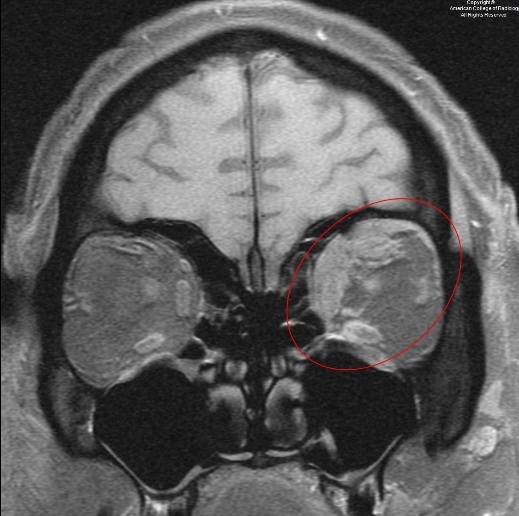

图 1 为平扫冠状 T1,示左侧眼眶上内侧异常信号(椭圆)